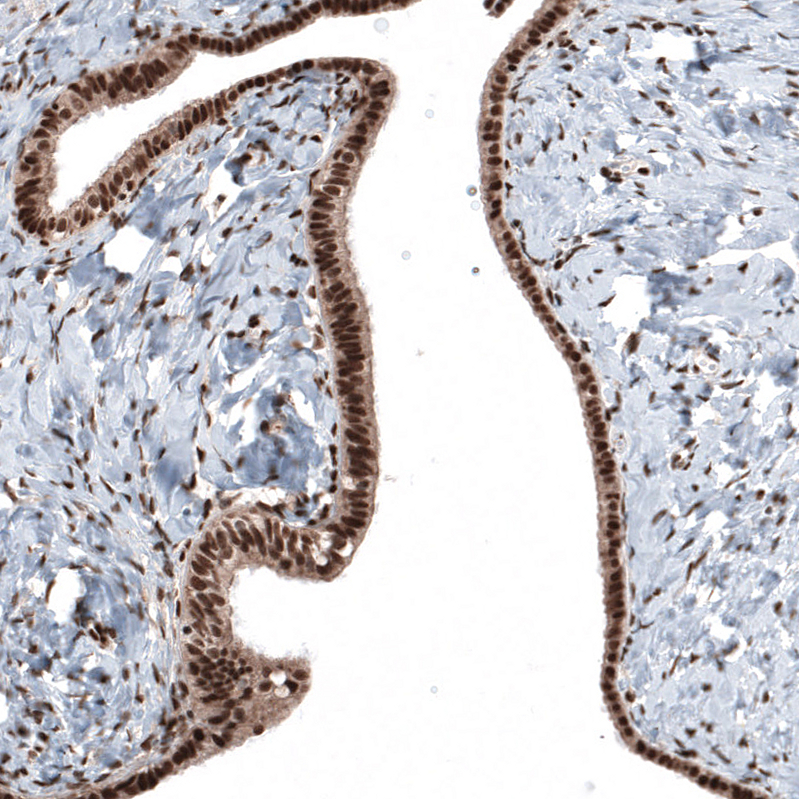

Immunohistochemical staining of human skin shows moderate nuclear positivity in squamous epithelial cells.